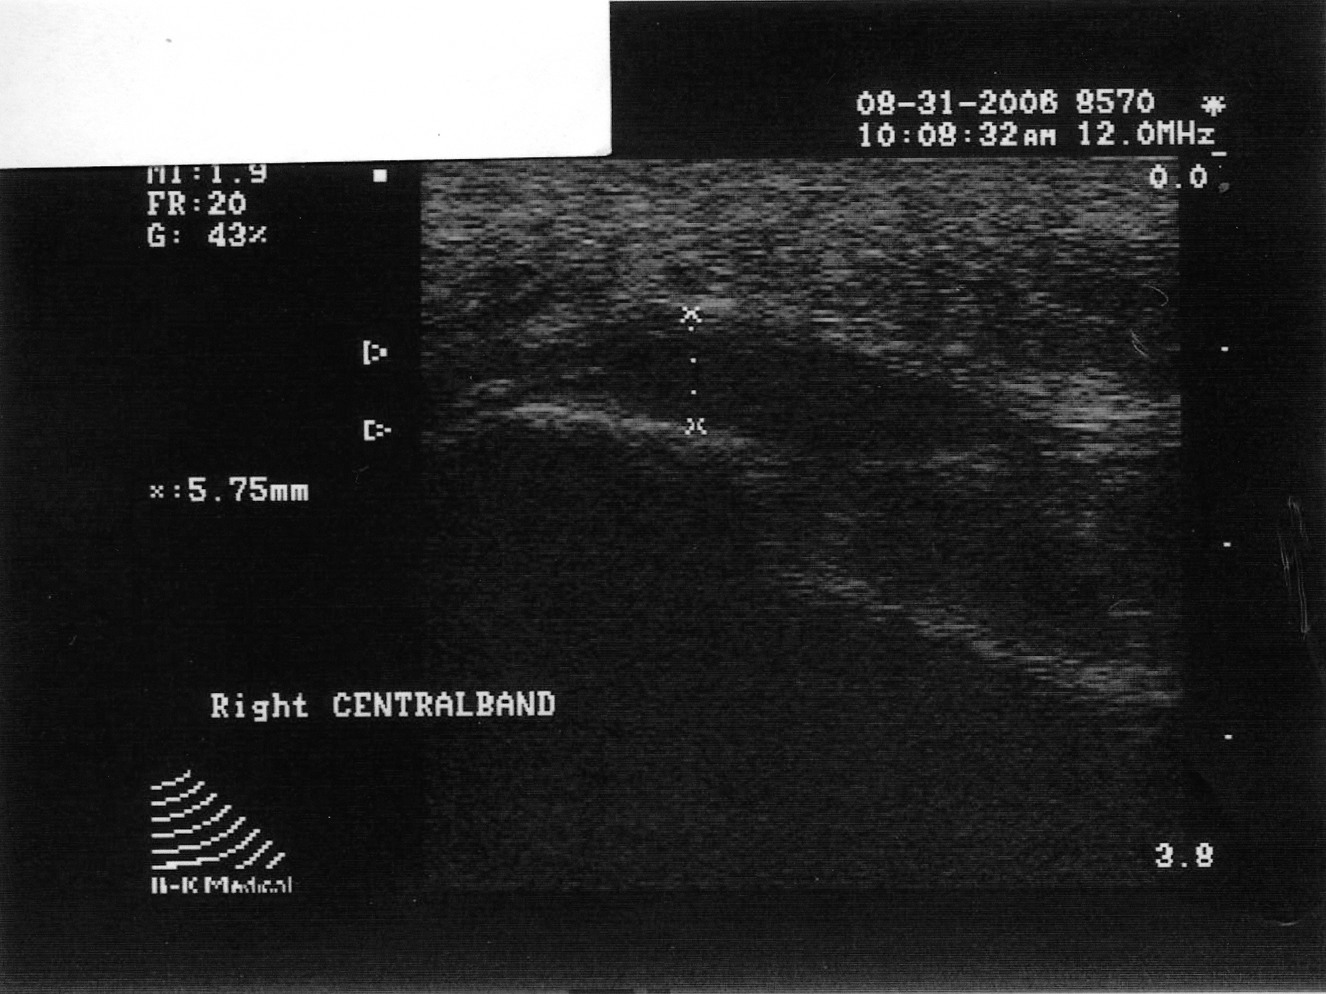

By utilizing musculoskeletal ultrasound imaging, the clinician can avoid frustration by identifying these esoteric etiologies earlier. One can also assess the severity of the problem. Indeed, clinicians can obtain quantitative measurements of the fascia and make (and document) qualitative assessments. Podiatrists can develop protocols and tailor treatment according to the severity of the condition. The more accurate assessment can help determine the success or lack thereof of the treatment plan that clinicians employ. One can scan the heel with the patient supine or prone. The preferred method is to have the patient in the prone position. Most clinicians lean toward this position because it tends to be easier for the examiner. Assess all three bands: medial, central and lateral. The examiner can scan in the long axis (sagittal plane) and the short axis (coronal plane). By far, the long axis will give the best information on the status of the fascia. One should assess the quality of the fascia. A normal fascia will have a fibrillar pattern. There will be anisotropy present where the fibers attach to the inferior aspect of the calcaneus. Take care not to confuse this with pathology. When documenting this properly, it is important to include a photo with the written description. Assessment then proceeds with measurement of the plantar fascia. Measure at the inferior aspect of the heel. Place the digital calipers at the hyperechoic line that represents the inferior aspect of the heel and the hyperechoic outline of the fascia at its most plantar expansion. (Just to clarify, the superior aspect of the image on the screen represents the plantar aspect of the heel. In other words, the image is inverted. By U.S. convention, the right of the screen should represent distal and the left of the screen would be proximal. Turning the probe 180 degrees will correct the orientation if one finds this not to be the case.) A fascial thickness of 4 mm has been mentioned as the upper limit of normal. When it comes to fascial thickness, I have even heard that one should consider upper normal limits of 4 mm for the medial band, 3 mm for the central band and 2 mm for the lateral band. Barrett, et. al., have looked at cadavers and plantar fascial thickness.1 It stands to reason that fascial thickness will vary depending on the size of the individual. I have seen this in my own practice. I have measured a patient’s normal fascia at 5 mm in thickness numerous times. Accordingly, when it comes to a unilateral case, one must compare the affected heel to the contralateral side. Another pitfall to avoid is including the deep musculature (i.e. flexor digitorum brevis) in one’s measurement. In some individuals, the muscular layer can be delineated deep to the fascia at the heel. Documentation of an ultrasound of the heel can be in a separate report or as a subset of the objective part of one’s notes. Either way, photos should accompany the written report. The assessment should include the measurements of all three bands of the symptomatic fascia and, in a unilateral case, the asymptomatic heel as a comparison. Along with the quantitative assessment, one should include a qualitative description as well and utilize proper terminology. Here are some of the more common terms: • Hyperechoic: increased echo or brightness on the screen • Hypoechoic: decreased echo or gray to dark on the screen • Anechoic: lack of echo or black on the screen • Fibrillar pattern: normal fiber pattern of tendon or ligament • Echotexture: general term referring to the internal architecture of the structure and the echo pattern seen